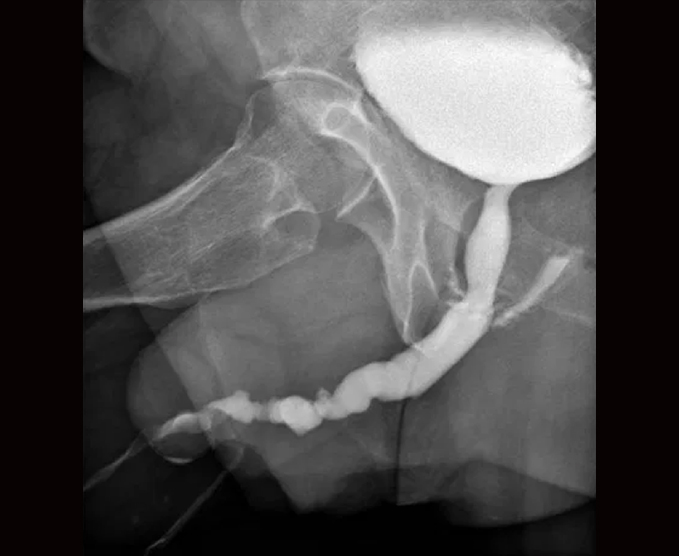

Algunos de nuestros estudios contrastados.

- Serie esófago gastroduodenal

- Colon por enema

- Urografía excretora

- Cistocrama miccional

- Cuello (Simple y contrastada)

- Uretografía retrógrada

- Fistulografías

- Tragos de hidrosoluble

- Esófagograma